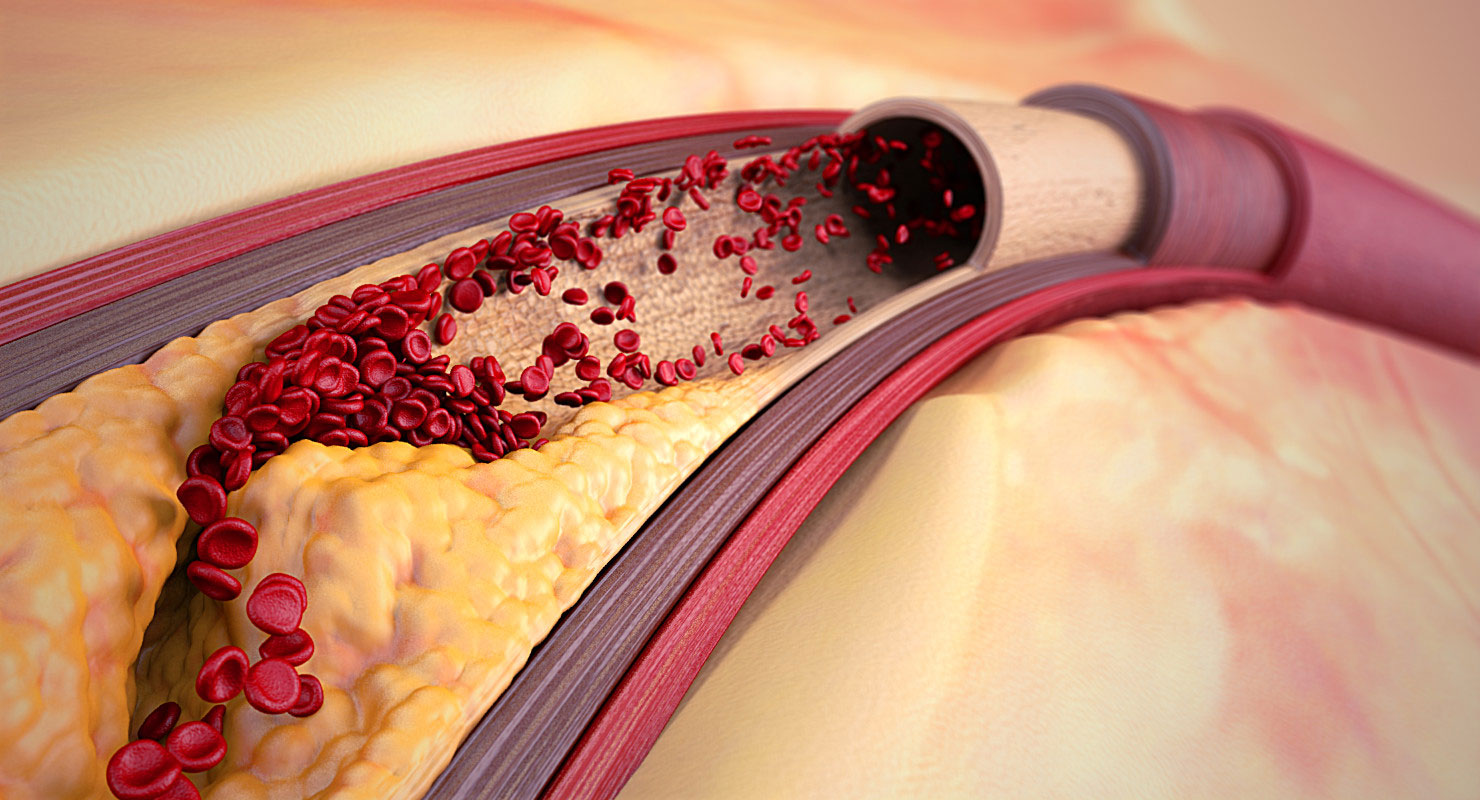

Изображения, связанные с атеросклерозом нижних конечностей и его лечением